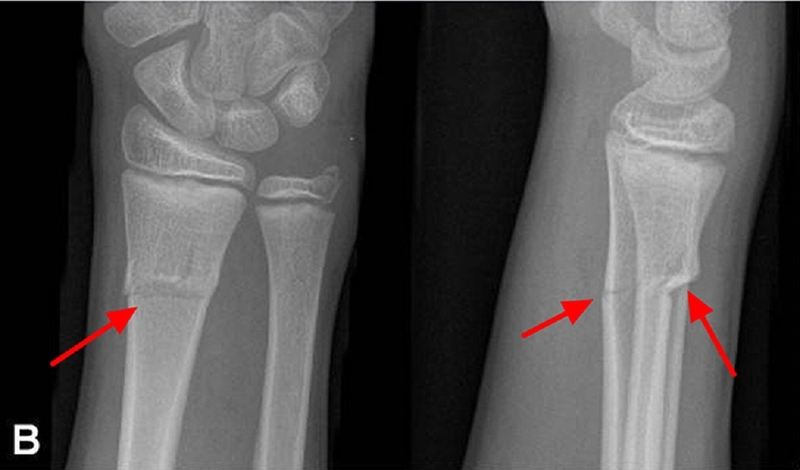

Gãy xương cành tươi thường được mô tả là gãy một phần hoặc không hoàn toàn, chỉ nằm ở một bên của thân xương, trong đó vỏ xương một bên bị gián đoạn, trong khi bên còn lại vỏ xương vẫn giữ nguyên.

Gãy xương cành tươi thường xuất hiện ở cẳng tay, khi xương uốn cong trước khi gãy và màng ngoài xương vẫn giữ nguyên. Xương gãy trong trạng thái này thường nằm bên trong màng ngoài xương.

Để đặt chẩn đoán chính xác cho gãy xương cành tươi, việc thực hiện chụp X-quang là cần thiết để hiển thị rõ hình ảnh về toàn bộ vết thương xương.